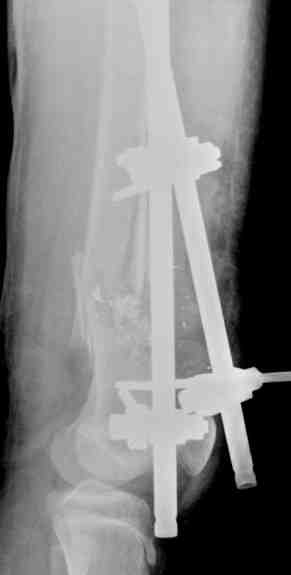

Выше представлены рентгенограммы открытого оскольчатого перелома нижней трети голени

X-rays of Compound Comminuted # Distal/3 Lt Tibia

Операционные снимки перед и после наложения аппарата Илизарова

In operation room before and after Ilizarov apparatus has been applied

Послеоперационные рентгенограммы

Postoperative X-rays

В нижнем ряду представлены рентгенограммы после окончательной репозиции.

And final reduction after Hexapod program has been finished